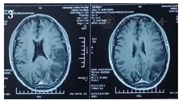

患者中年男性,反复卒中发作,伴有认知下降,外院以"病毒性脑炎"治疗效差,患者外院两次头颅磁共振提示左侧颞枕叶呈现类花边征样改变,且第二次磁共振(图2)提示病灶较第一次(图1)范围扩大,但前次磁共振病变在第二次磁共振呈现好转趋势,呈现"此消彼长"的特点,增强磁共振未病灶未强化(图3),头颈CTA未见异常(图4);患者发病来无四肢抽搐,根据病史及影像学定位为:大脑皮层、枕叶、左侧锥体束、左侧脊髓丘脑束,定性考虑:卒中?代谢性?炎性?感染?

患者入院前磁共振检查:

患者中年男性,反复卒中发作,伴有认知下降,外院以"病毒性脑炎"治疗效差,患者外院两次头颅磁共振提示左侧颞枕叶病变,第二次磁共振比第一次病灶面积增大,且磁共振提示病灶为分层样改变,患者发病来无四肢抽搐,根据病史及影像学定位为:大脑皮层、枕叶、左侧锥体束、左侧脊髓丘脑束,定性考虑:卒中?代谢性?炎性?感染?结合患者卒中样发作;影像学表现;认知障碍、血乳酸显著增高、磁共振波谱成像显示病灶、≥2次卒中样发作、患者母亲有糖尿病史、肌电图提示周围神经受累、体重下降、卒中样发作急性期病灶弥散加权成像(DWI)弥散受限,皮质受累尤为明显,呈现类花边征样改变。病灶具有进展性、可逆性、多发性以及呈现"此消彼长"的"游走性"特点[3,4]。